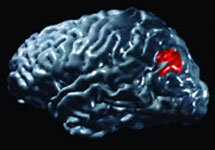

"Мы старались, чтобы обезьяны не ошибались в ходе этих тестов, однако случались и серии ошибок, - поясняет Олбрайт. - И нам стало интересно, что же происходит в их мозгу, когда обезьяны делают явно неверный выбор, несмотря на то, что они наверняка должны были бы помнить правильную связь пары символов". И вот в то время как обезьяны пробовали вспомнить - то есть восстановить правильные ассоциативные связи - и делали-таки свой ошибочный выбор, ученые стали наблюдать сигналы от невроцитов (нервных клеток, нейронов) в этой самой нижней височной коре головного мозга. А теперь уже точно известно, что эта область критически важна для процессов визуального распознавания различных структур и к тому же отвечает за работу именно этого типа памяти.

После того, как Олбрайт и его группа проанализировали картины активности мозговых клеток в нижней височной коре, они сделать вывод о том, что более 50 процентов тамошних активных невроцитов можно смело отнести к особому новому классу нейронов, в которых, как считают исследователи, и закодирована память о правильных соединениях "стимула" и связанного с ним символа.

А самым удивительным во всей этой истории кажется то, что эти специализированные мозговые клетки продолжали посылать свои "правильные" импульсы даже тогда, когда обезьяны выбирали символы неверные. "В этом смысле мозговые клетки "знают" больше, чем обезьяны обнаруживают своим поведением", - говорит Олбрайт. Ведь в реальном мире обезьян (как и людей) все время что-нибудь отвлекает, то есть не дает как следует сосредоточиться и сбивает с правильных мыслей, не позволяет обратиться к истинной памяти...